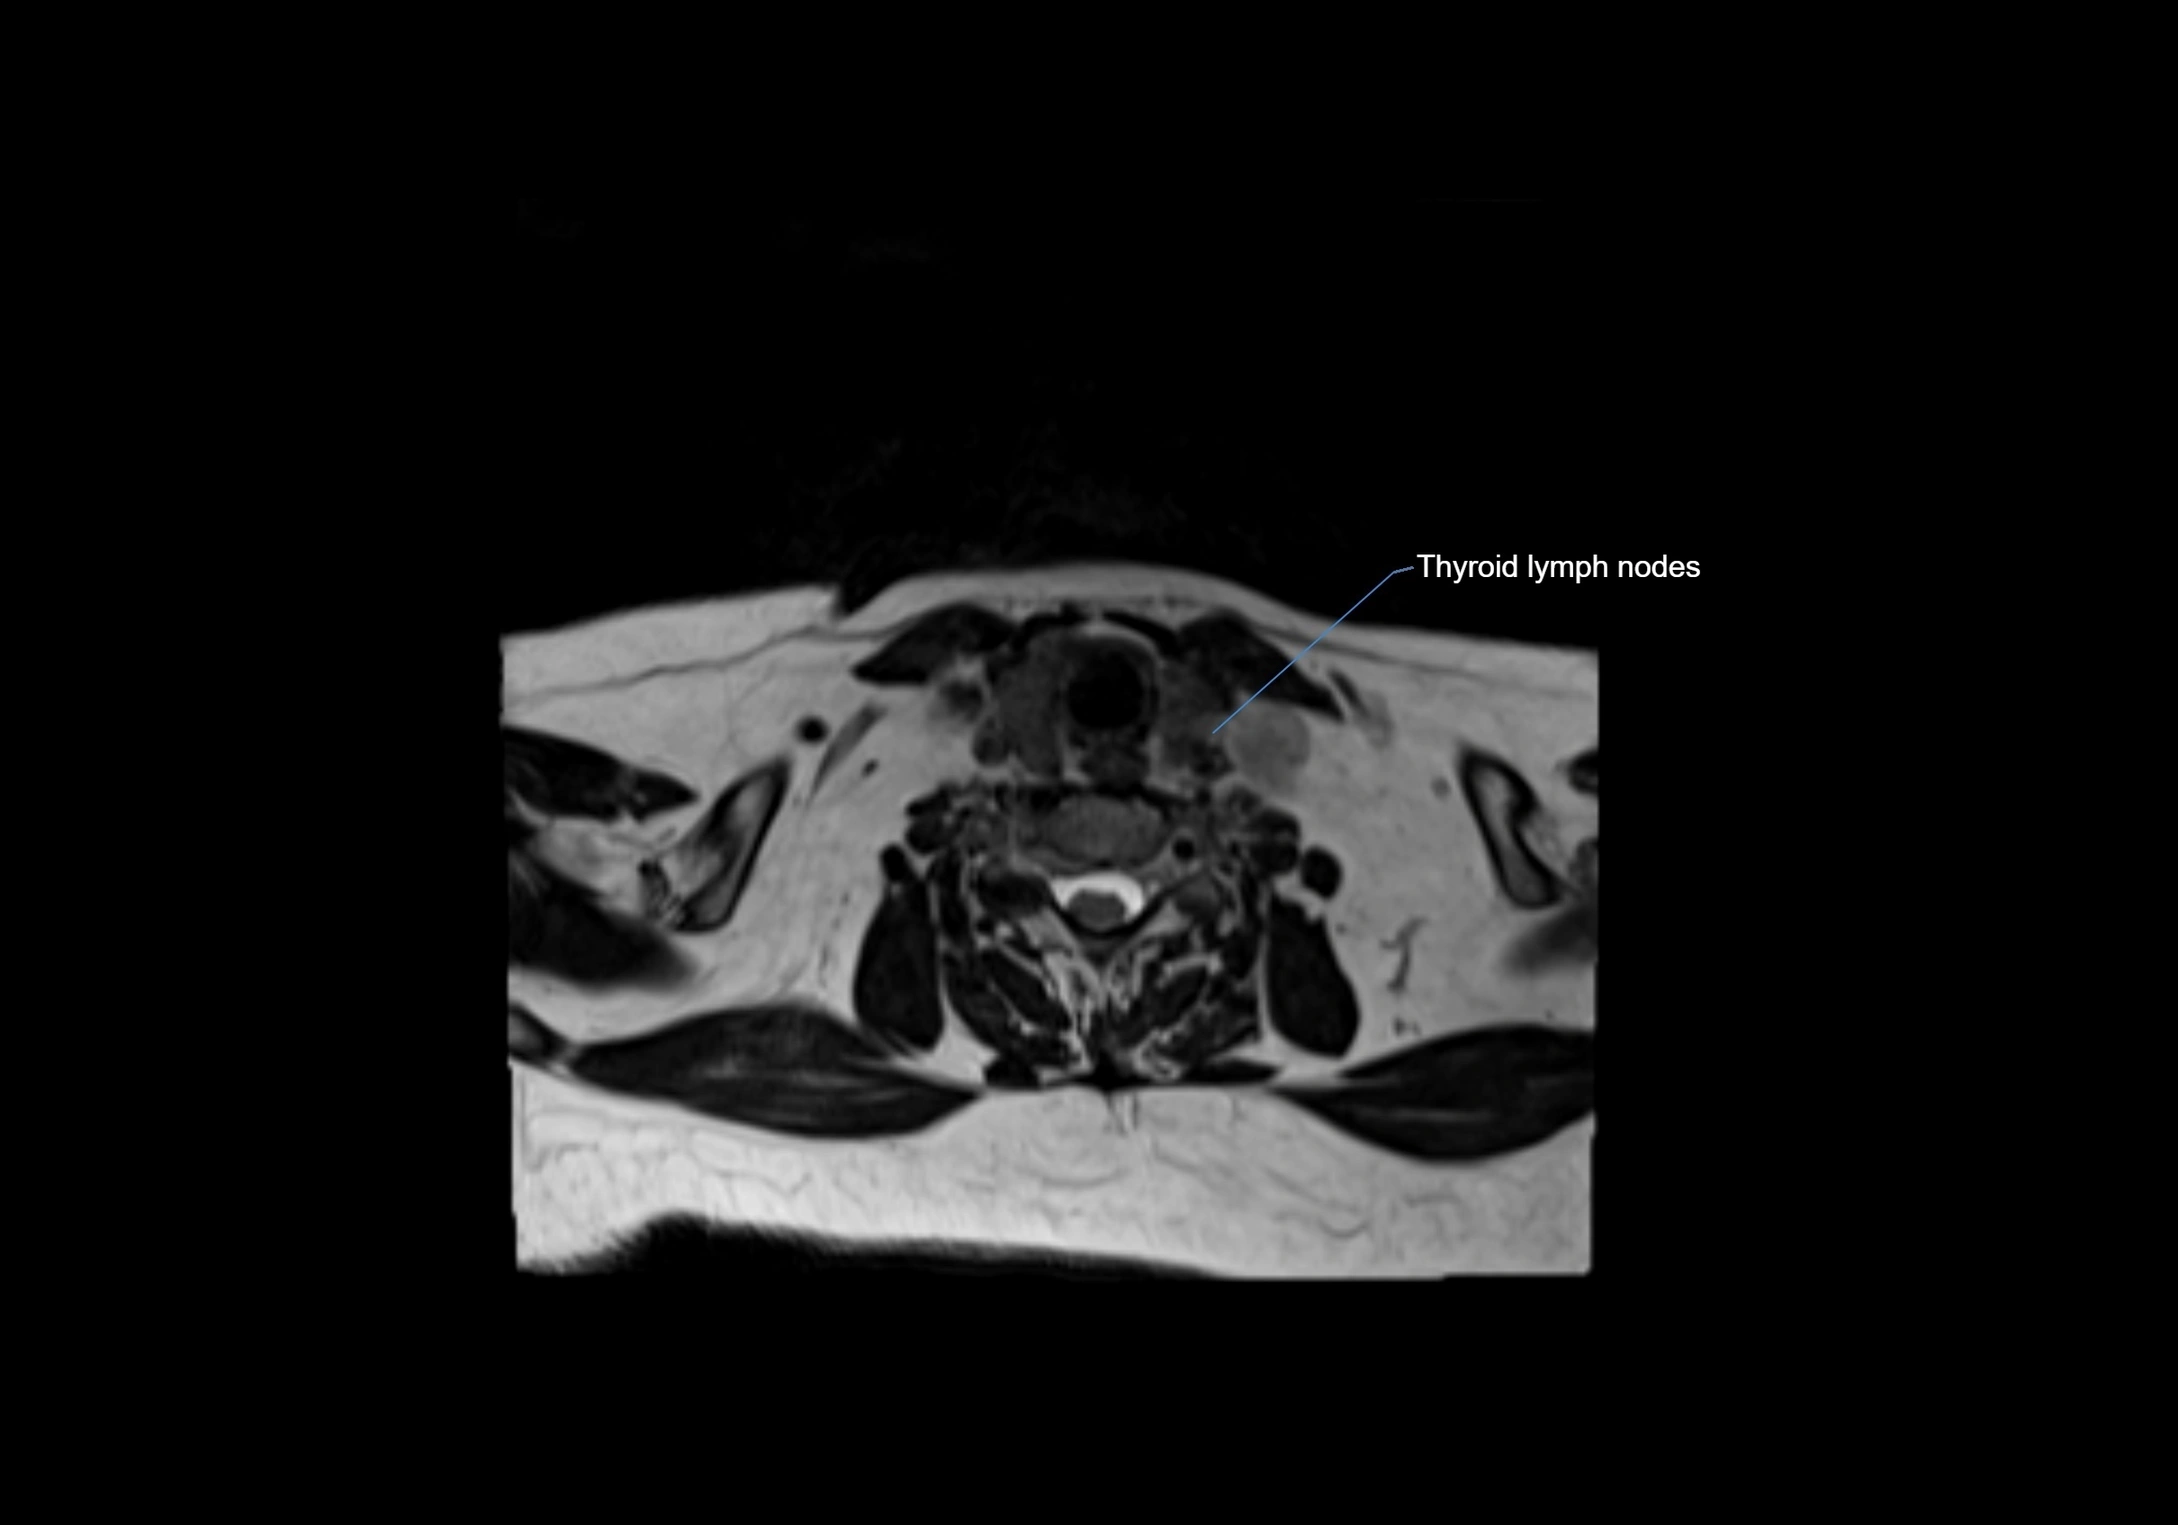

Accessory lymph nodes are small, secondary lymph nodes located along the main facial and cervical lymphatic chains, often adjacent to primary lymph nodes, such as preauricular, submandibular, or occipital nodes. They are typically less than 5 mm in diameter, embedded within subcutaneous fat or connective tissue, and may be variable in number and location. These nodes provide additional filtration and immune surveillance for lymph collected from the face, scalp, and neck regions. Accessory lymph nodes are usually non-palpable in healthy individuals but may enlarge in response to infection, inflammation, or metastasis, making them clinically significant.

• Found along primary lymph node chains, including preauricular, submandibular, parotid, and occipital regions

MRI Appearance

T1-weighted images:

• Normal accessory nodes appear as small, oval hypointense to intermediate signal structures within subcutaneous fat

• Surrounded by hyperintense fat, enhancing contrast for visualization

• Pathological nodes may appear enlarged or rounded, sometimes with cortical thickening

T1 Post-Contrast (Gadolinium-enhanced):

• Normal nodes may show mild, homogeneous enhancement

• Inflamed or metastatic nodes demonstrate marked homogeneous or heterogeneous enhancement, highlighting the cortex and fatty hilum

• Post-contrast imaging helps detect early metastasis, infection, or inflammatory changes

T2-weighted images:

• Nodes show intermediate signal, with surrounding fat bright

• Useful for detecting edema, inflammation, or infiltration

• Fatty hilum may appear slightly hyperintense relative to cortex